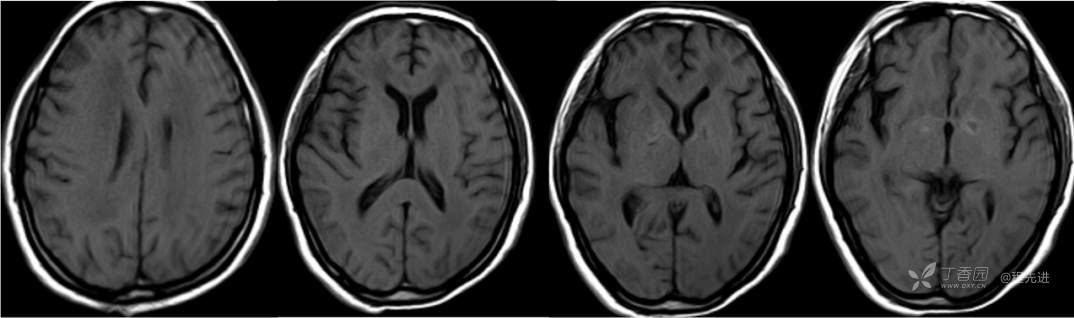

MR

T1